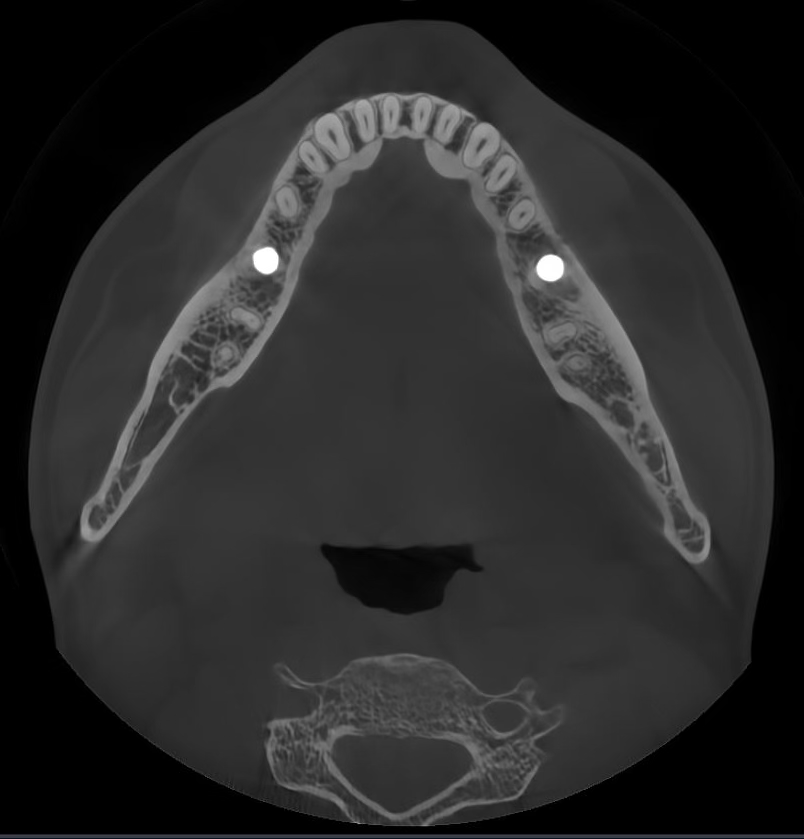

Los algoritmos matemáticos que reflejan las propiedades físicas y el avanzado motor de IA aprendido a partir de varios datos trabajan juntos para reducir el ruido y hacer que las estructuras dentales sean más claras.

Borra los artefactos metálicos y restaura con precisión las estructuras dentales, las coronas metálicas y los implantes basados en principios matemáticos.